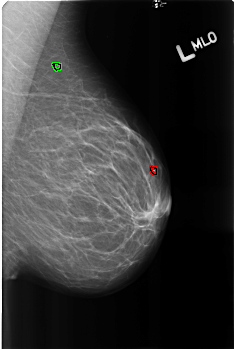

B_3165_1.LEFT_MLO

LEFT_MLO LINES 4528 PIXELS_PER_LINE 3032 BITS_PER_PIXEL 12 RESOLUTION 50 OVERLAY

FILE: B_3165_1.LEFT_MLO.OVERLAY

TOTAL_ABNORMALITIES 2

ABNORMALITY 1

LESION_TYPE CALCIFICATION TYPE LUCENT_CENTERED DISTRIBUTION N/A

ASSESSMENT 2

SUBTLETY 4

PATHOLOGY BENIGN

TOTAL_OUTLINES 1

BOUNDARY

ABNORMALITY 2